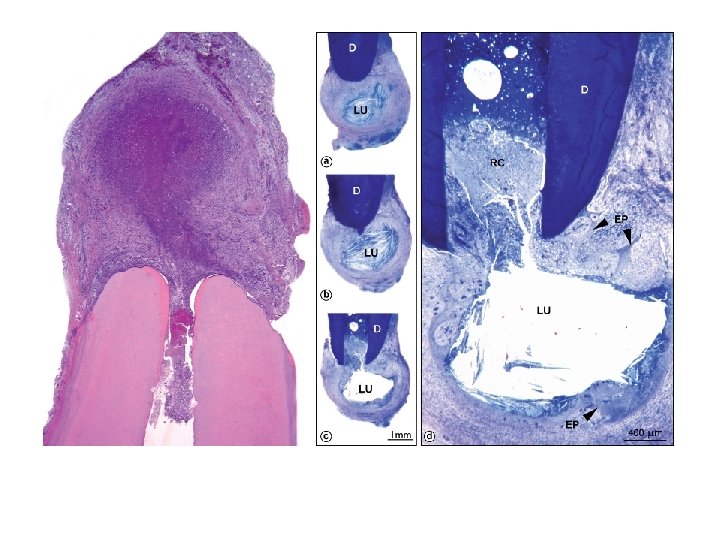

Ricucci & Bergenholtz 2004

Vital, inflamed: reversible-irreversible pulpitis Haapasalo & Endal Microabscesses can heal Mjør & Tronstad 1972

Apical root resorption Traumatic; aseptic Traumatic; infective